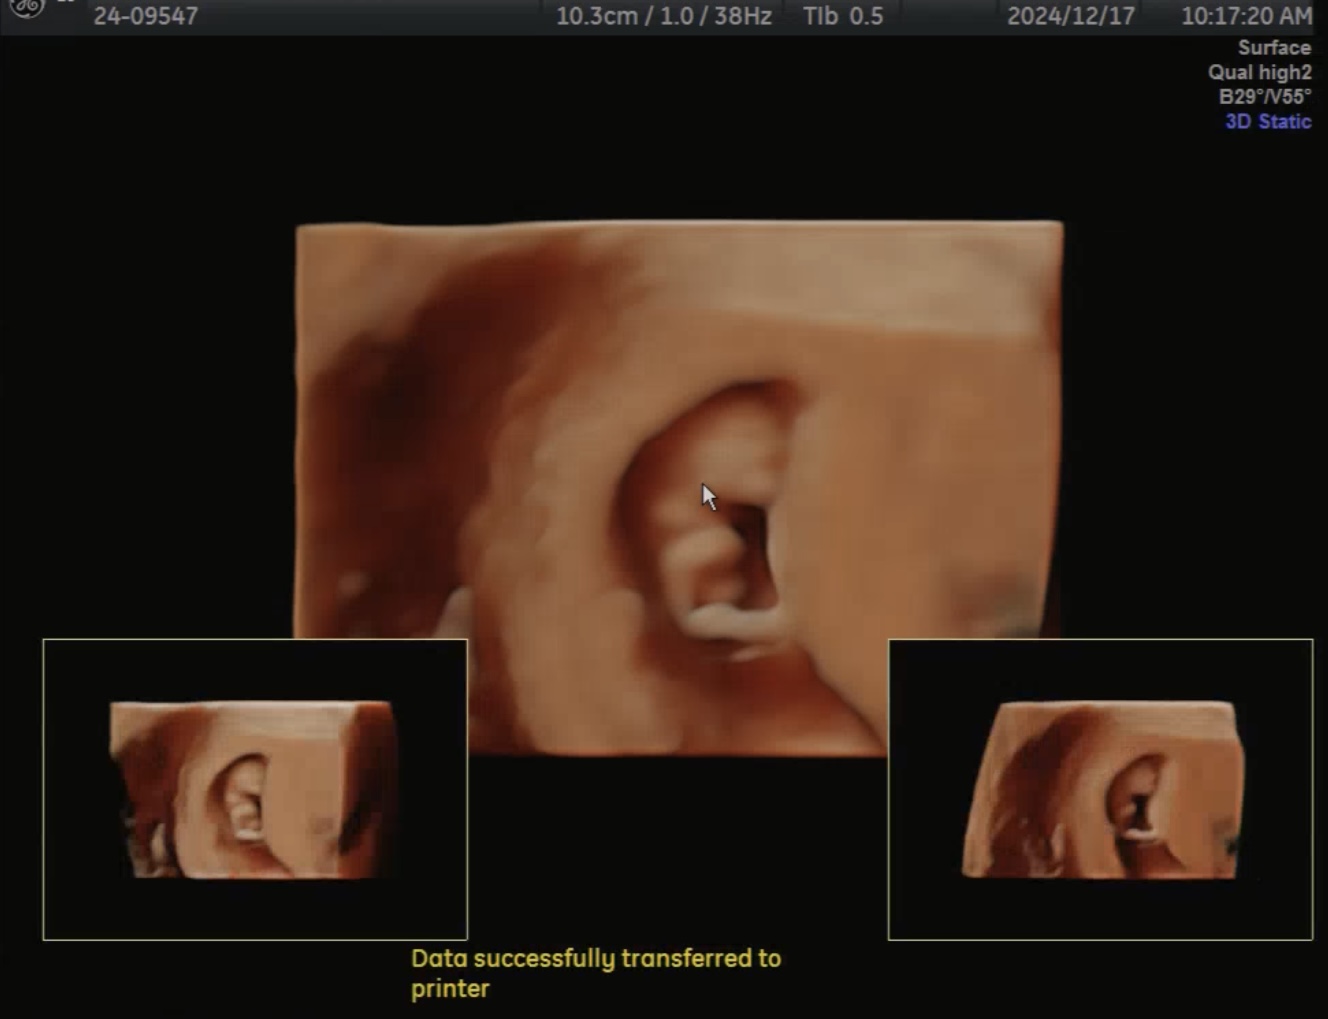

입체 초음파도 처음 보고 왔다.